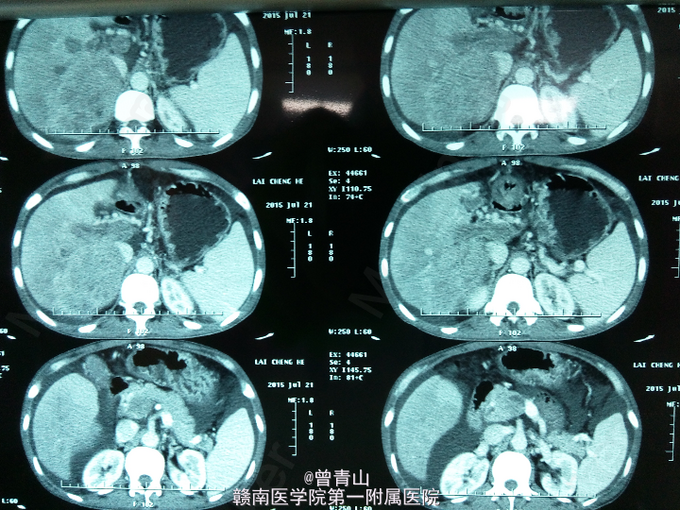

查体:腹部稍膨隆,硬,全腹可及轻度压痛及反跳痛,肝肋下右锁骨中线处4cm处可触及,脾脏未触及,肝区叩击痛阳性,移动性浊音阳性,肠鸣音弱,未见肝掌及蜘蛛痣。辅助检查:血分析:红细胞(仪器法)3.99*10^12/L,中性细胞比率85.91。甲胎蛋白(化学发光)104517ng/ml。凝血功能:(AT3)AT-Ⅲ51.3%,凝血酶原时间14.2s,D-二聚体4.84mg/L。尿分析:蛋白质1+,酮体1+,白细胞55.6/ul,管型20.81/ul,浊度1+。大便常规正常。肝功能:天门冬氨酸氨基转移酶(速率法)47U/L,总蛋白(双缩脲法)55.8g/L,白蛋白(溴甲酚绿法)30.3g/L,总胆红素(酶法)22.9umol/L,直接胆红素12.6umol/L。乙肝表面抗原>>225.000ng/ml,乙肝核心抗体>>4.020PEIU/ml。上腹部增强CT提示:肝增大,肝右叶见10.0*12.5cm大小低密度肿块,增强扫描早期呈不均匀强化,门静脉期与延迟期呈低密度,门静脉主干与左右分支内见低密度充盈缺损,门静脉周围见多发性迂曲血管影。

患者目前诊断:肝右叶原发性肝细胞肝癌并门静脉癌栓形成。处理:给予护肝、补液、营养支持等对症处理。由于患者肝癌并门静脉癌栓形成,一般情况较差,在我院的技术尚不能给患者行手术治疗,也无其余更好的治疗方法,建议去肝胆外科知名度高的医院就诊。